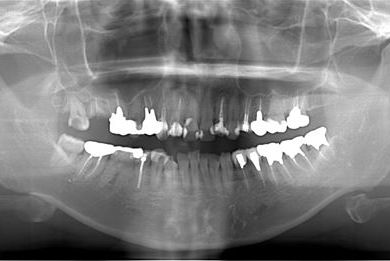

| 性別/年齢 | 女性 / 34歳 | ||||||||||||||||||||||||||||||||

| 主訴 | 現在痛みはなく、前歯の汚れを治したい。奥歯はブリッジを考えている。審美を考えているが、今治療をしたいというよりは、セラミックなど詳しいことがわからないので、計画や説明を伺いたい。 | ||||||||||||||||||||||||||||||||

| 治療方針 | 上前歯部分、セラミック治療にて審美的回復を行う。 | ||||||||||||||||||||||||||||||||

| 治療内容 | オールセラミッククラウン3本(オールセラミック用土台3本)、メタルボンドセラミッククラウン1本 | ||||||||||||||||||||||||||||||||

| 総治療費 | 562,800円 | ||||||||||||||||||||||||||||||||

| 治療期間 | 8ヶ月 |